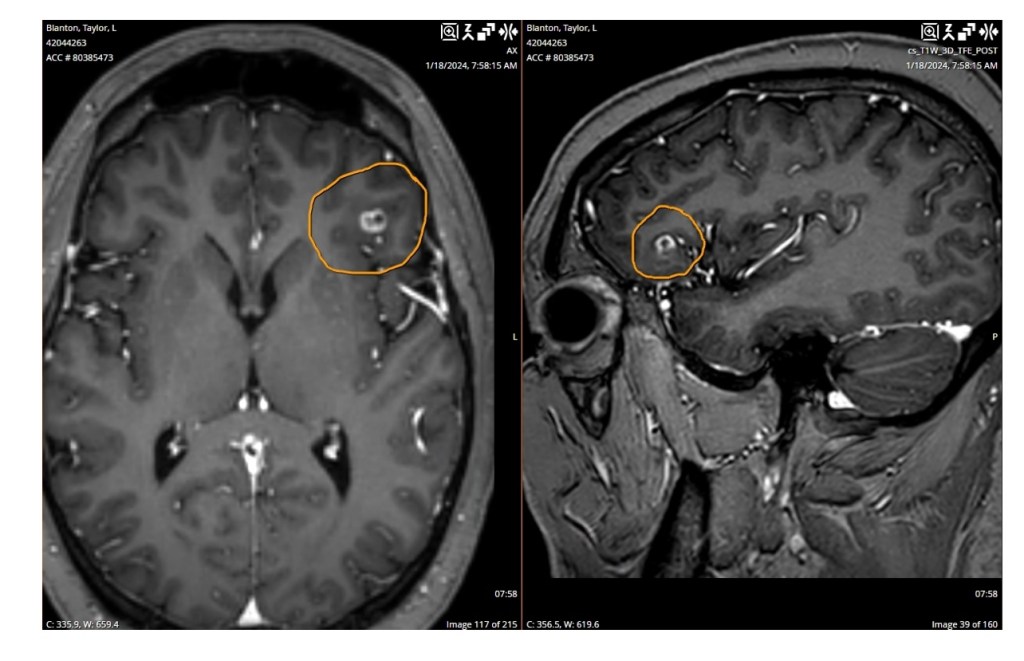

I began immunotherapy alongside radiation because tumors kept growing like wildflowers, and I kept having brain bleeds. The immunotherapy hadn’t had enough time to work so I was back to a waiting game. I was up to 27 brain tumors and 5 brain bleeds at that point. The holidays came back around again and this year wasn’t any better than the last. The doctors had started hinting that I should really try to enjoy the holidays because it could be my last one. But I just didn’t wanna do them. The steroids had made me gain 75 pounds, I was always angry, and I had pushed everyone away. I was miserable! I got to the point that I kept asking God to just go ahead and take me. What was the point? I was so tired. I went from being healthy and strong to having flutters, discovering heart cancer, to fighting terminal brain cancer.

I didn’t lean on Him through my chemo, open heart surgery, and stroke. I leaned on science and the flesh. I started to ask Him what He could teach me through my diagnosis and how I can help others with my testimony. And I truly have a testimony because I have had open heart surgery, 18 rounds of chemo, a massive stroke, 27 brain tumors, and 5 brain bleeds with almost no outward deficits that anyone would notice besides my family and myself. Every time I go to the doctor they say I’m a walking miracle. We don’t know how you’re alive but keep fighting. It’s only by the grace of God that I’m here and able to type this out. I’ve recently re-dedicated my life back to the Lord and I study the Bible daily. I don’t know where this journey will take me spiritually but I’m writing this blog to tell my testimony to give people hope. Learn like I did how to follow the flutters Jesus puts in your heart. No matter how hard the road is, you have to trust and lean on Jesus. If you don’t you’ll be just like Peter when he saw the waves and storm and started to sink. We have to have BIG Faith and TRUST God with all our being! I feel him working in my life!